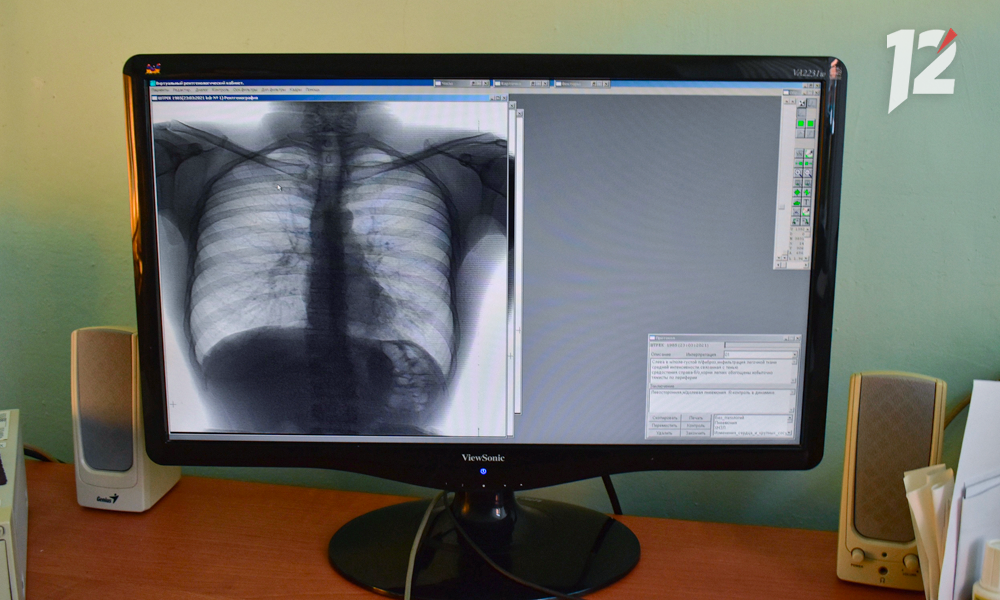

— Не стоит паниковать. Нужно сесть, подумать, что не так. А потом с этими жалобами обратиться к своему «родному» участковому терапевту или педиатру. Все доктора обучены, как проводить диагностику туберкулёза. У детей проводят пробы Манту и «Диаскинтест», у взрослых — плановую флюорографию. Терапевт сначала обратит внимание на их результаты. А потом уже проведёт клинический минимум исследований и направит к фтизиатру, если в этом будет необходимость.